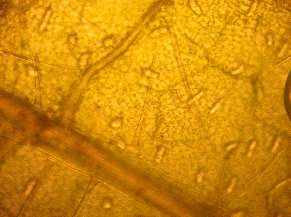

.1.2 Микроскопический анализ

При микроскопическом исследовании препаратов

листа с поверхности обнаруживаются простые многоклеточные волоски с

бородавчатой кутикулой и головчатые волоски с одноклеточной ножкой и

обратнояйцевидной одноклеточной головкой. Устьица диацитные. По поверхности в

углублениях видны многочисленные эфирномасличные железки (рис. 4). Эпидермис

извилистостенный (рис. 3). [1]

Рис. 3. Извилистые стенки эпидермиса

Рис. 4. Эфирномасличная железка